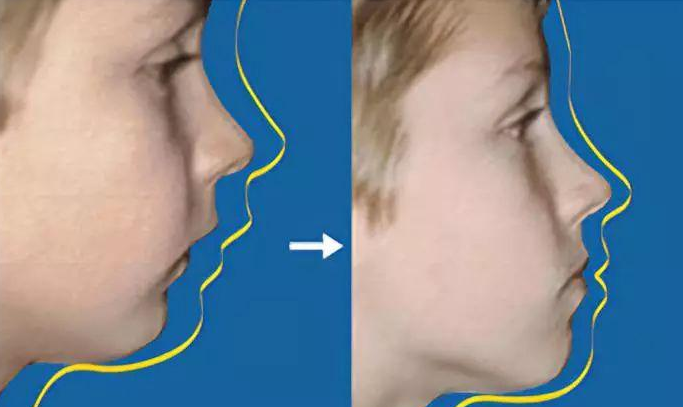

影响颜面美观

牙颌畸形影响颜面美观是最直观的,如地包天、开唇露齿、下颌偏斜都会使人的整体形象大打折扣。

影响口腔及面部发育

儿童生长发育期间的牙颌畸形如不能及时早期矫治,将会影响口腔及颜面部软硬组织的发育,引起面部的明显畸形。如地包天、开唇露齿等。